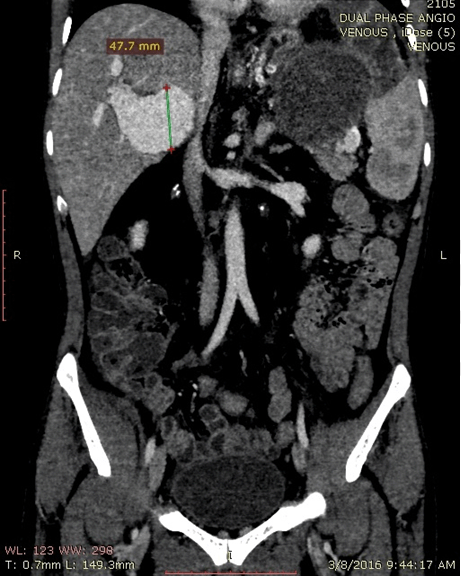

A 56-year-old male with no known medical comorbidity presented with complaints of vague upper abdominal discomfort associated with nonspecific left sided headache for one month and fever on and off for 15 days. On examination, he was conscious, comfortable and cooperative with a blood pressure of 130/70 mmHg and a pulse rate of 84/min. On abdominal examination, there was fullness in the epigastrium with tip of the spleen palpable below the left costal margin. Computed tomography angiography of the abdomen revealed a large heterogeneous mass near the splenic hilum measuring around 9×8.3 cm in the axial plane and approximately 8.6 cm in its craniocaudal extent in relation to the tail of pancreas bulging into the lesser sac and abutting the greater curvature of stomach with faint contrast uptake along the periphery with another large hyperdense mass within, consistent with a large splenic artery aneurysm containing a thrombus (Figure 1). On the arterial phase scan, there was minimal enhancement within this lesion. The spleen was enlarged with an infarct in its lower pole. The liver was grossly normal with no nodularity. There was an aneurysmal dilatation of the portal vein at the porta hepatis, measuring 47.7 mm in the largest diameter (Figure 2).

Figure 1: Computed tomography angiography image showing the splenic artery aneurysm with an organized clot within and the portal vein aneurysm (47.7 mm) on the transverse section.

Figure 2: Computed tomography angiography (coronal section) image showing minimal enhancement of the splenic artery aneurysm on the arterial phase with minimal portal venous phase enhancement; Portal vein aneurysm enhancing well on the venous phase.